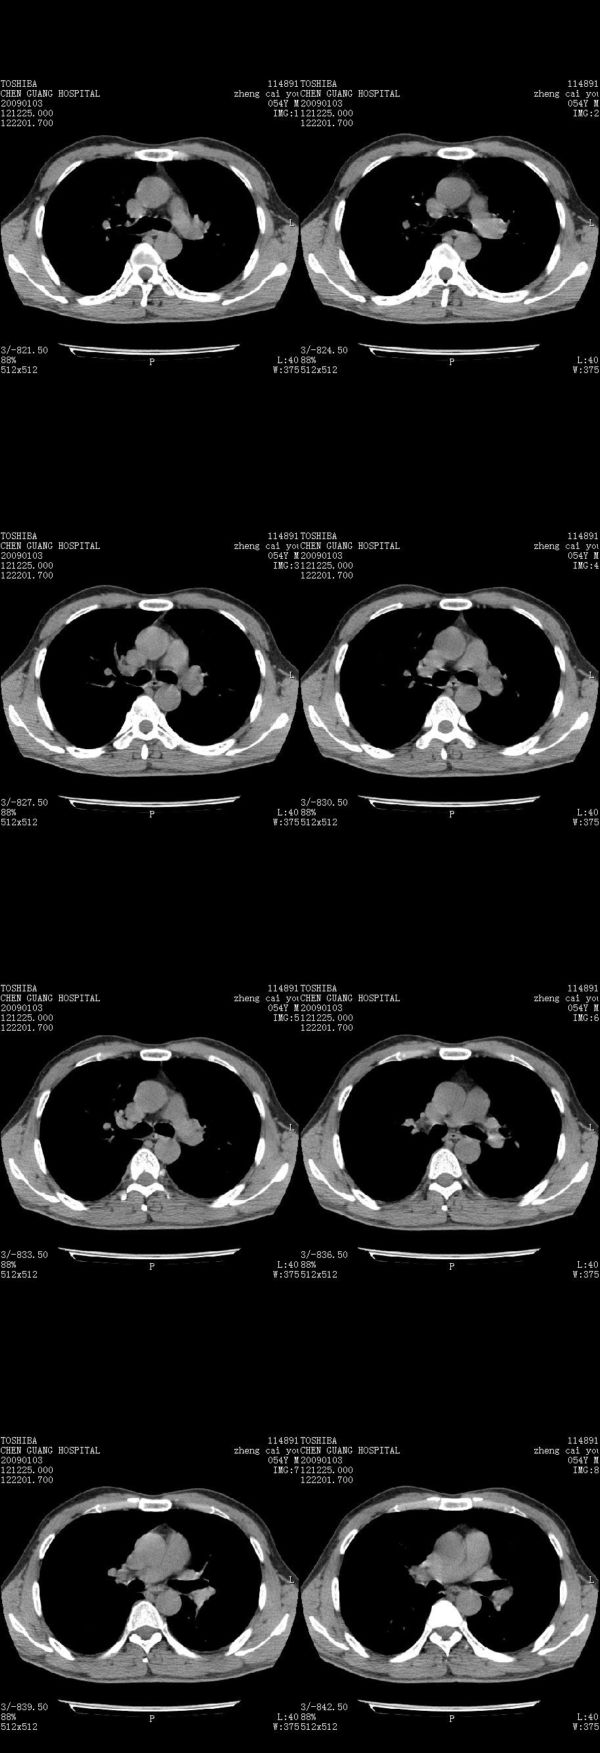

男,54岁,右侧胸部疼痛,平时吸烟,有抽烟后咳嗽咯痰史。昨天没把xiphoid软件吃懂,所以没把纵隔窗图像处理出来!请各位老师帮忙看一下右肺门有没有问题?谢谢!!!!!!!!!!

右肺上叶后段近气管旁仍可见一结节灶,不除外为肿大的淋巴结影。

气管前腔静脉后似见增大淋巴结影,肺门区未见明显肿块影。肺窗示右肺中叶外侧段透亮度增高,可过一段时间再查一下对比一下,毕竟是自己的至亲,又有条件,辐射就顾不得了。

也觉得还好吧,只是右下肺动脉显粗了点,纵膈有钙化淋巴结,再有肺窗就更好了

各位老师:奇静脉增宽,肺上未见明显实变,这还需注意观察些什么?????

右侧肺门影增大,不除外增大淋巴结可能